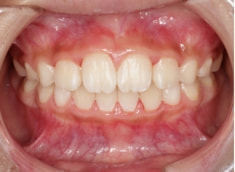

症例紹介

小児期ケース:叢生(ガタガタ)

治療法:拡大プレート+フルパッシブブラケット(クリアスナップ)

治療前

治療後(8ヶ月後)